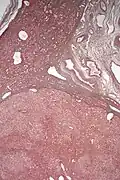

Micrograph of a hepatic adenoma (bottom of image). H&E stain

Hepatic adenomas are, typically, well-circumscribed nodules that consist of sheets of hepatocytes with a bubbly vacuolated cytoplasm. The hepatocytes are on a regular reticulin scaffold and less or equal to three cell thick.

Cells resemble normal hepatocytes and are traversed by blood vessels but lack portal tracts or central veins.